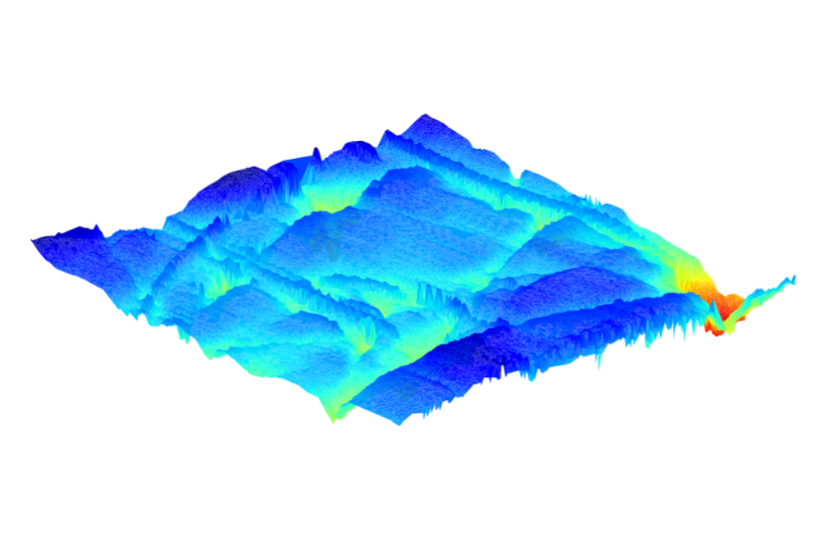

LC-OCT™ imaging of the back of a hand